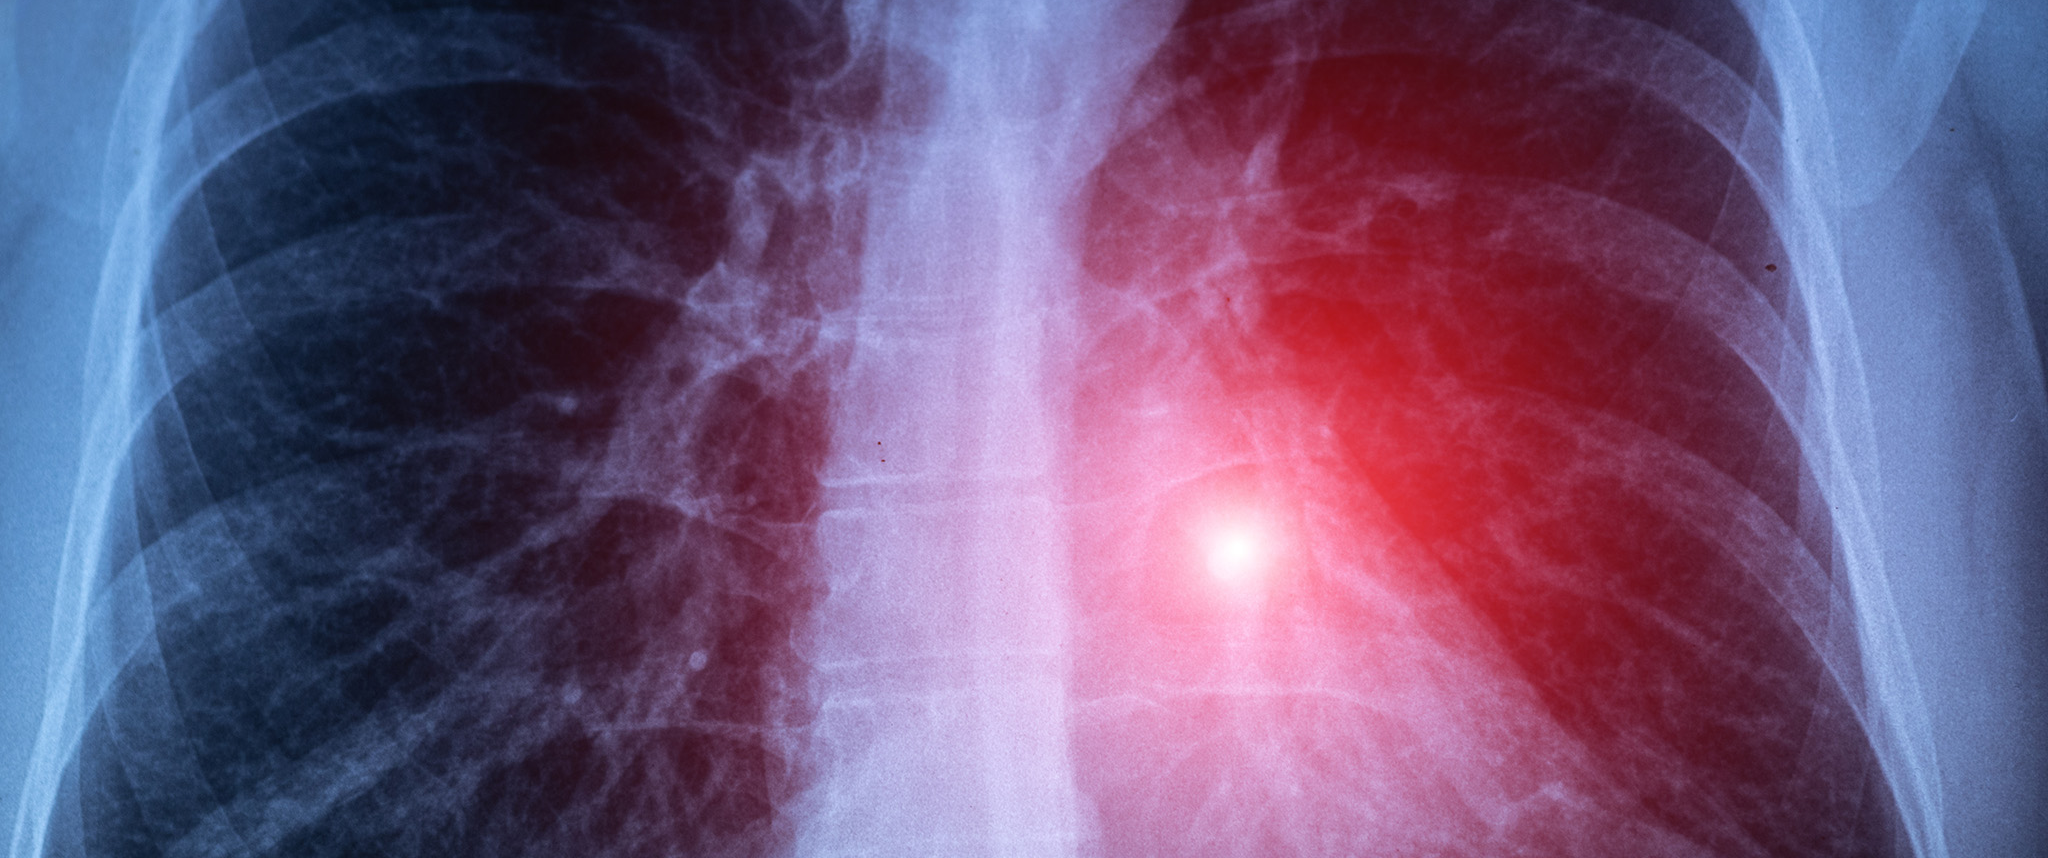

A lung X-ray shows glowing cancer cells.

“We were talking about ways to do this operation better, and we identified a possibility to inject patients with contrast agents that fluoresce, or glow,” says Dr. Singhal.

This initial spark led eventually to the Center for Precision Surgery, launched in 2016. The group, which now includes 110 members, has conducted 16 clinical trials to develop a cadre of fluorescent contrast agents. These aides to imaging are injected into patients and taken up by sarcomas, and tumors in the ovary, lung, and brain. In these tissues, they make cancer cells glow so that surgeons can locate the lesions and remove them more completely.